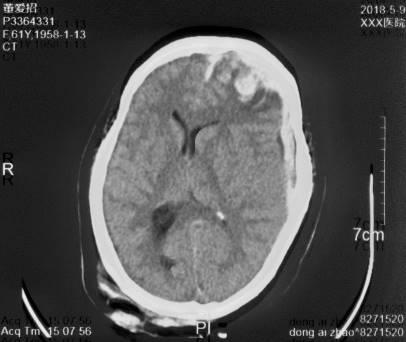

复阅2020年4月29日CT片:左侧额颞部颅骨修补、脑积水分流术后改变,人工颅板在位,双侧额颞叶、左侧枕叶及右侧小脑半球见片状低密度阴影,左侧脑室较右侧稍扩大,内见引流管在位。提示左侧额颞部颅骨修补、脑积水分流术后,双侧额颞叶、左侧枕叶及右侧小脑半球软化灶形成。

图13-15,2020年4月29日 CT片,左侧额颞部颅骨修补、脑积水分流术后,双侧额颞叶、左侧枕叶及右侧小脑半球软化灶形成。